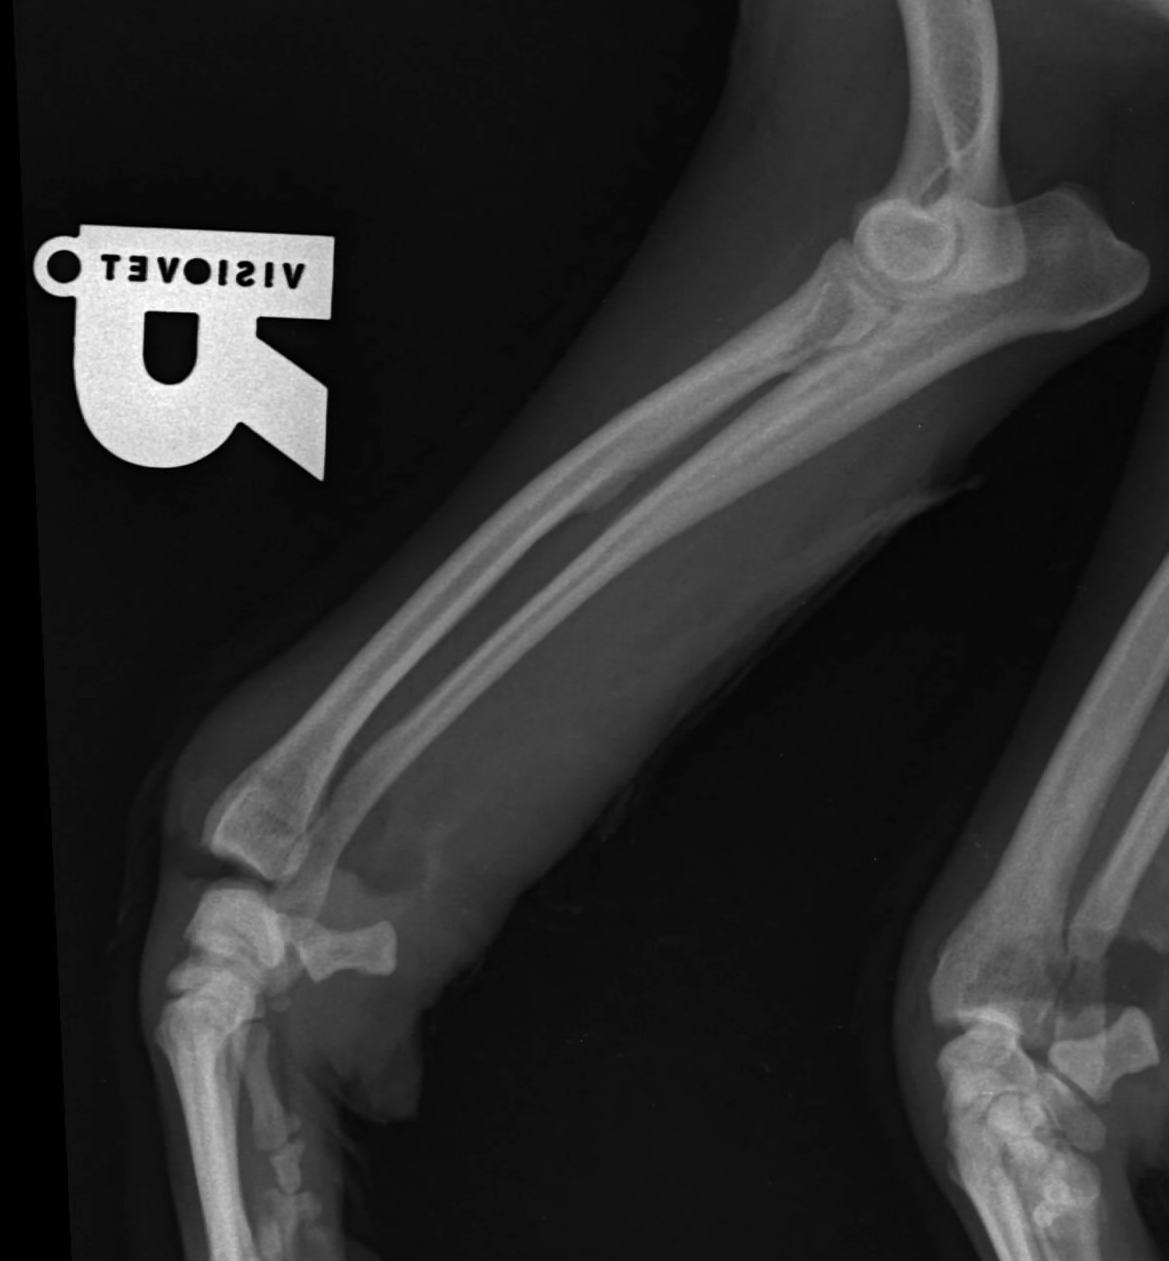

Validarea poziționării corecte a plăcii în raport cu osul și a selecției adecvate a dimensiunii și numărului șuruburilor s-a făcut prin examenul imagistic radiografic convențional, utilizând incidențele clasice, respectiv incidența medio-laterală și incidența caudo -cranială (figura 6 a și b). Investigațiile imagistice postintervenție au relevat că spațiul articular scapulo-humeral, capul humeral și cavitatea glenoidă, precum și spațiul articular humero-radio-ulnar, epicondilii humerali, trochleea humerală, fosa olecraniană și gaura supratrochleară au rămas integre, iar placa a acoperit întreaga diafiză humerală.

Romanian Journal of Veterinary Orthopedics and Imagistic - Figura 6. Imaginea radiografică a brațului după fixarea plăcii – incidență caudo-cranială (a) și medio-laterală (b) Adelina Proteasa, Roxana Dascălu, C. Igna